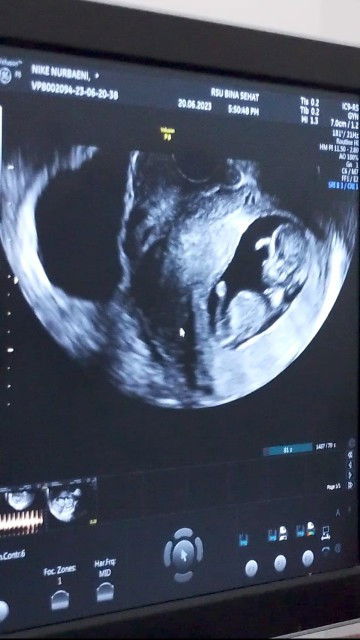

Plasenta lepas sebagian

Moms,ibu saya hari ini ada jadwal periksa lagi ke obgyn karena pas Minggu ke 8 didiagnosa abortus imminens,pas diperiksa kata dokter plasenta sebagian lepas kira" penyebabnya apa ya moms,yang ditunjuk ditanda panah itu darahnya